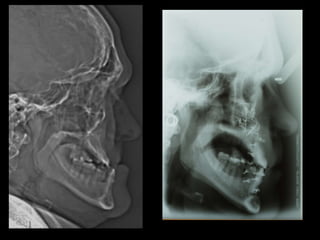

Hiperplasia condílea dcha

Anquilosis ATM dcha

Anquilosis ATM Hiperplasiacondílea Cirugía ortognática